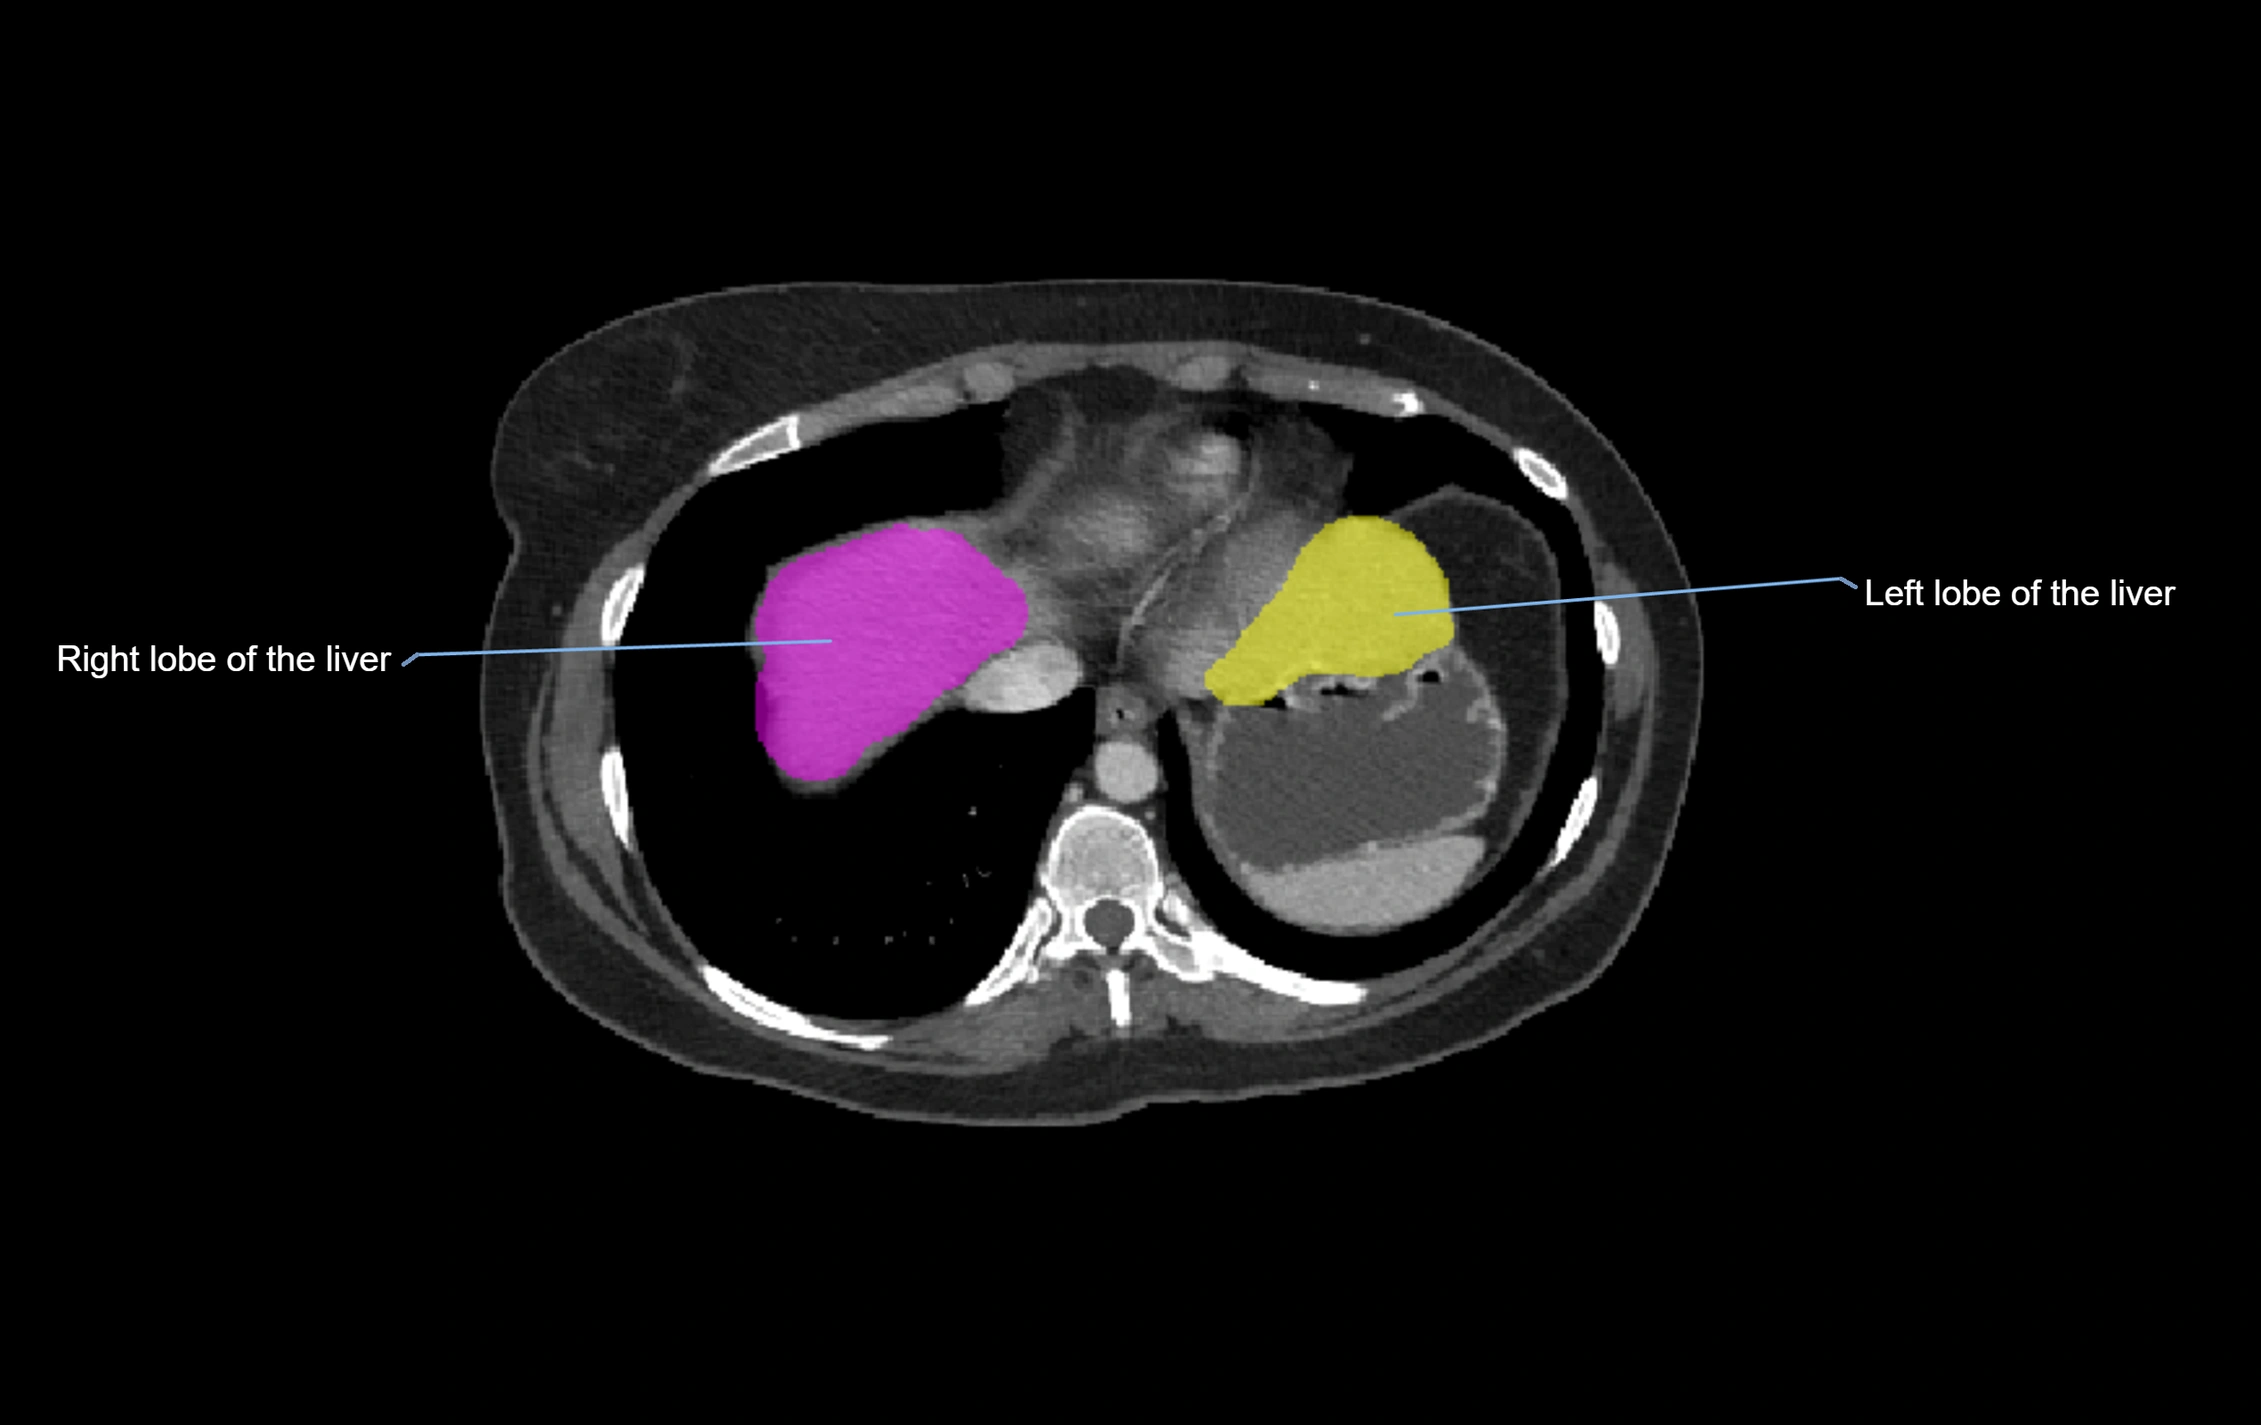

CT Image

image